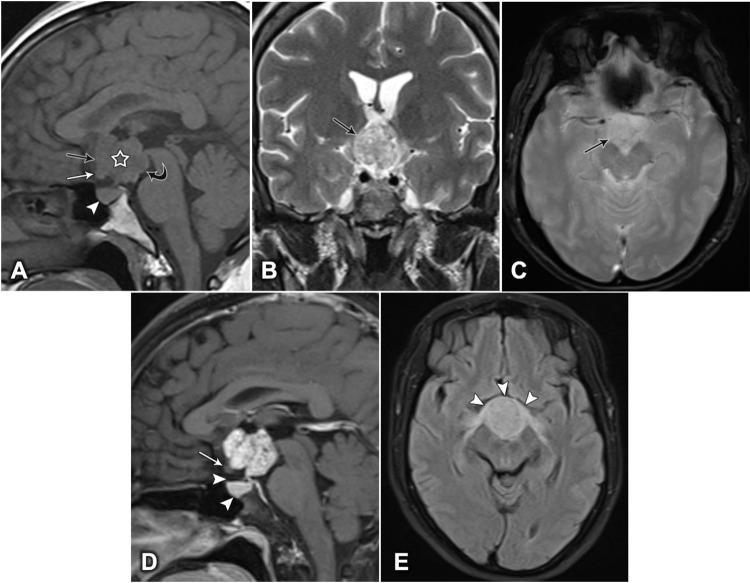

We aimed to describe the magnetic resonance imaging features observed in five cases of strictly intrinsic third ventricular papillary craniopharyngiomas, including two cases of mixed cystic and solid tumors and three cases of pure solid masses.

Among the adult population, intrinsic third ventricular papillary craniopharyngiomas should be considered when either solid or mixed cystic and solid masses are observed, in which the solid component shows heterogeneous intensity, heterogeneous and strong enhancement, and is strictly located in the third ventricle.

我们旨在描述5例严格意义上的第三脑室内乳头状颅咽管瘤的磁共振成像特征,其中包括2例囊实性混合肿瘤和3例纯实性肿块。

在成人中,当观察到实性或囊实性混合肿块,且实性成分表现为不均匀信号强度、不均匀且明显强化,并严格位于第三脑室内时,应考虑第三脑室内原发性乳头状颅咽管瘤。